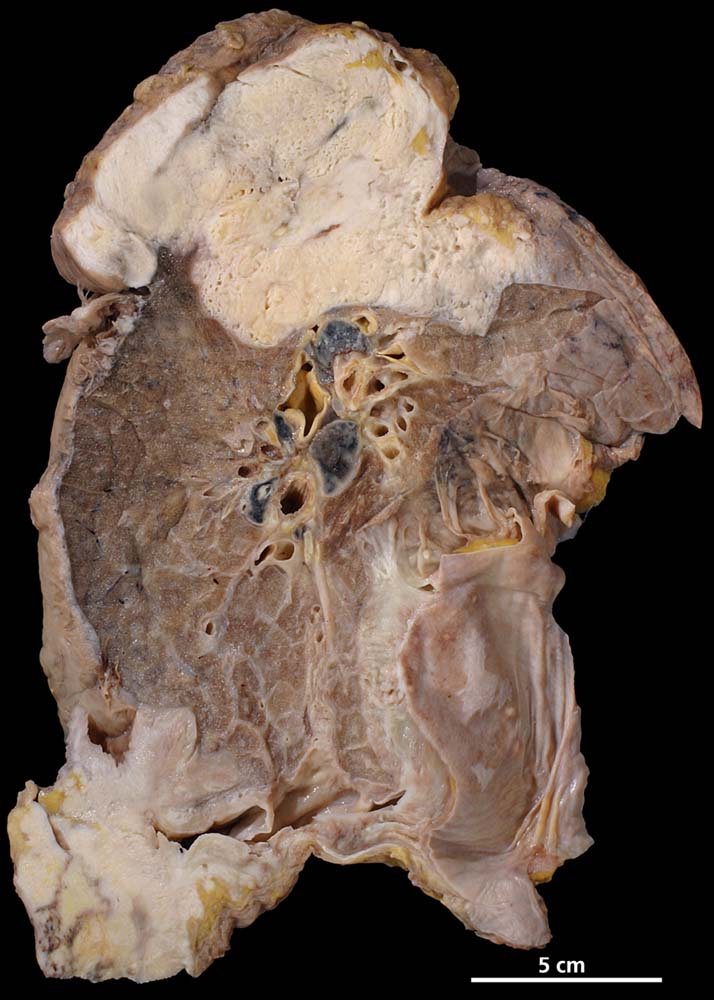

Grosszelliges Bronchuskarzinom

Pseudomesotheliomartige Ausbreitung im Bereich der Pleura, akzentuiert in zwei grossen (7x6x4cm bzw.13x14x2cm), teilweise nekrotischen Tumorherden im linken Unterlappen und im apikalen Anteil des linken Oberlappens mit Einwachsen ins Perikard.

Wenig differenziertes, grosszelliges Karzinom

Pleuraerguss und Lungenembolien. Maligne Zellen im Pleuraerguss. Verdacht auf Bronchus-Ca des linken Unterlappens mit mediastinalem Lymphknotenbefall.